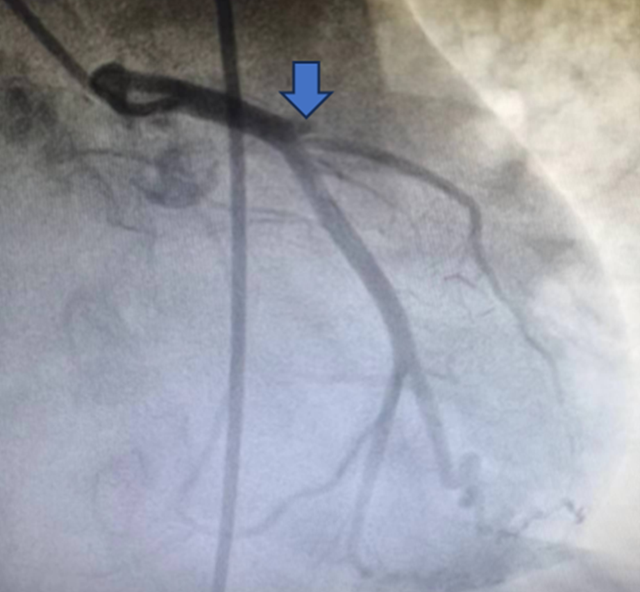

2月26日上午12:50分,李大爷被送入导管室,由于李大爷大面积心肌梗死导致血压低,并且处于昏迷状态,魏刚当机立断,指导当地心内科医生直接穿刺股动脉而不是常规的桡动脉,为李大爷进行了冠状动脉造影、冠状动脉支架植入手术。凭借丰富的经验,手术用时不到20分钟,穿刺、造影、支架植入一气呵成,顺利帮助李大爷闯过了冠状动脉梗阻“关”。

(患者冠脉支架植入前、后对比图)